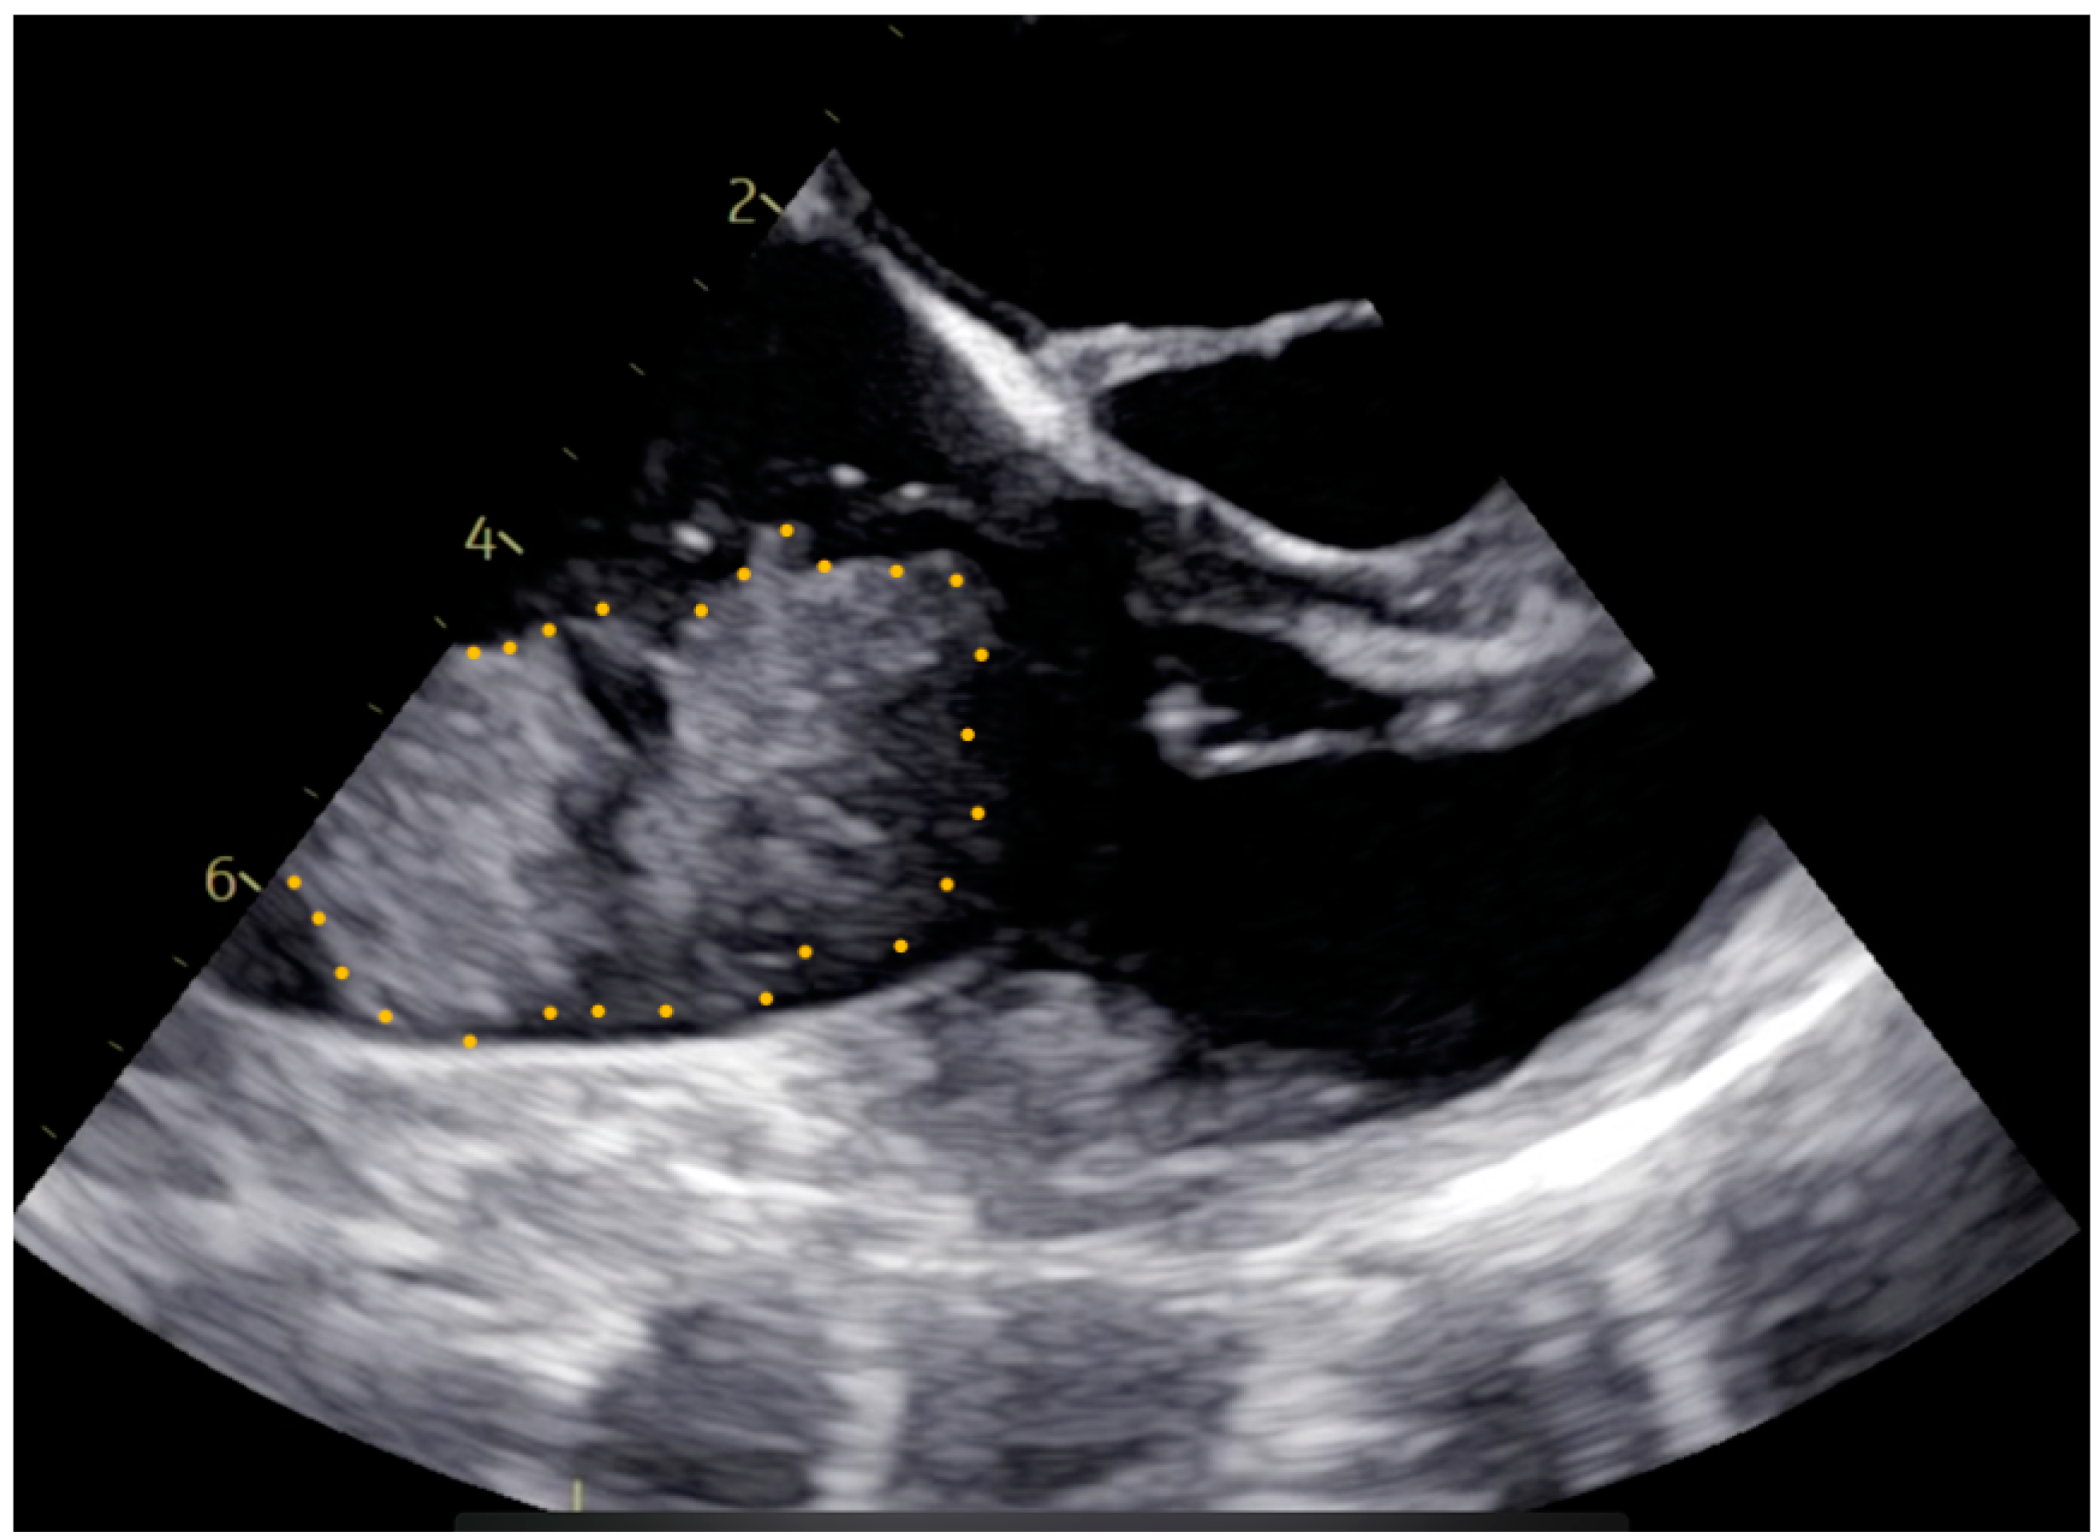

Pre-operative cardiac magnetic resonance imaging (MRI) and transesophageal echocardiogram (TEE) revealed a myxoma measuring 46 mm × 37 mm × 30 mm in the right atrium. The base of the myxoma, located around the basal posterior wall of the right atrium, appeared to extend to the tricuspid valve and right ventricle (Figure 1 and Figure 2). Despite the localization and considerable size of the myxoma, there was no significant tricuspid valve insufficiency, and the function of both the left and right ventricles remained within normal parameters. The patient was evaluated for open-heart surgery involving the removal of a myxoma, with consideration for tricuspid valve replacement.

Figure 1. Pre-operative transesophageal echocardiogram image. The myxoma boundaries are delineated with a dotted yellow line.